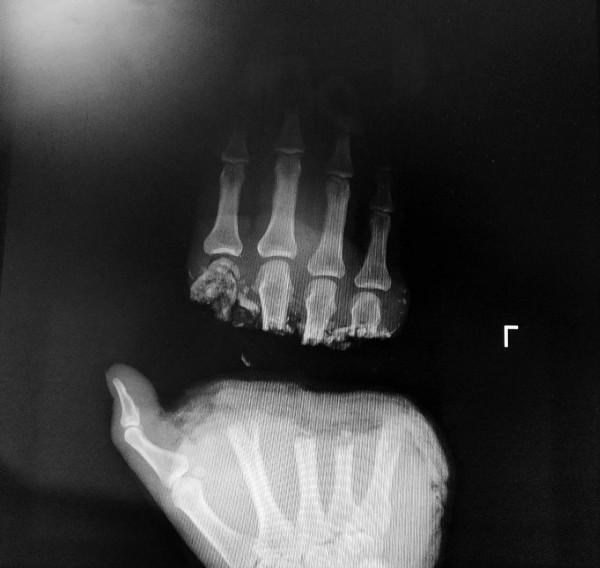

日前,一名外地工人被礦石切斷了左手,斷處正齊手掌橫紋,而橫紋處是手掌血管總彙集處,因此該處血運複雜,續接困難。患者在斷手10小時後,經哈醫大一院創傷骨科團隊共同努力,經過10個多小時的手術,連闖“三關”,將傷者的手續接成功!

第三關:血管縫合——斷掌處為手部血管匯合處,四處動脈與五處靜脈是必須連線的

斷指連線的時候,需要指到兩根動脈和四根靜脈相連即可,而對於陳某的手外傷,則需要找到四根動脈與五處靜脈。因為患者的斷掌處位於手部血管的匯合處,如果血管接不全,就會導致其他指末端出現缺血的現象,也就意味著手術失敗。

掌端的動脈比較好找,滲血的地方就是,但是五處的靜脈又在哪裡?這是考驗每個骨外科醫生最難的問題。